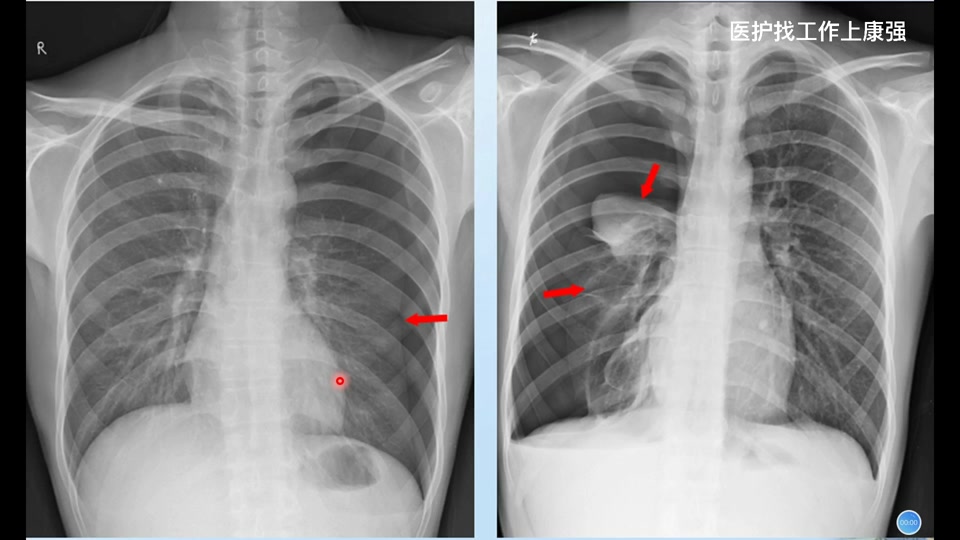

2021年3月30日 首都医科大学附属北京胸科医院医学影像科左肺上叶微结节2年余北京胸科医院CT加急,结核诊断性治疗1年胸科医院ct提示左肺上叶结节见饱满不排除恶性可能左肺上叶结节。2025年

2021年3月30日 首都医科大学附属北京胸科医院 医学影像科 左肺上叶微结节2年余北京胸科医院CT加急,结核诊断性治疗1年胸科医院ct提示左肺上叶结节见饱满不排除恶性可能左肺上叶结节。